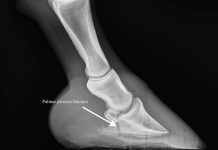

Equine Coffin Bone Fractures – The Horse

How coffin bone fractures occur, and how you can stop them from changing into career-ending accidents